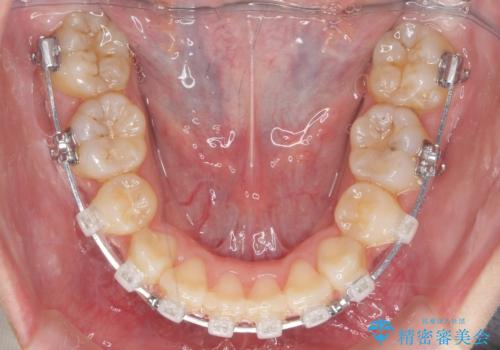

- ワイヤー矯正

- 前歯のがたつきを主訴に来院。

顔が小さく、顎に大きな歯が入りきらない状態でした。

抜歯してワイヤー矯正を行いました。